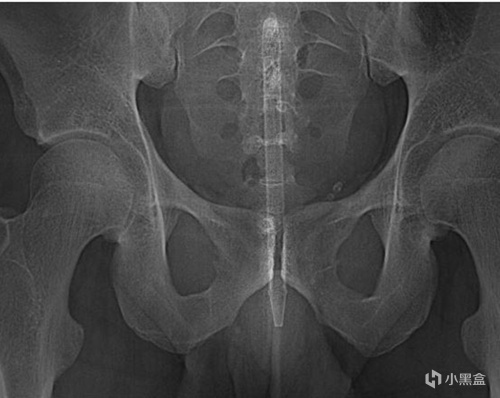

上面有我接診過的患者,也有來源網絡的圖片。但是這種誤入體內的異物,可能有電子產品或者瓶子,甚至也有活物進入的情況。大多數直腸異物發生sex的過程中,被取出的異物包括但不限於按摩棒,橡膠聖劍、高爾夫球、白熾燈等等(也經常有毒販通過包裝好的袋裝毒品藏入胃裏或者直腸裏來販毒)。有一些異物可能一開始已經被完全容納進去,深入體內後難以取出。

比如這位患者在嘗試用夾鉗自救取出異物,可惜一起折戟在體內了不得已就診。

直腸異物典型症狀就是排便困難、腹痛、便血,甚至腸梗阻。如果嘗試自救,反覆磨蹭還可能導致肛管、直腸部分的黏膜水腫和肌肉痙攣,進而更難取出異物。而且最好不要輕易嘗試在不確定異物種類和位置的情況下,做直腸檢查。要不然容易導致異物破裂,造成二次傷害。

一般在直腸鏡下通過夾鉗和牽引取出位置較低的異物,高位的就需要結腸鏡和手術取出了。總結來說,這屬於人禍導致的,無論是否是自己主動塞進去異物,最後都需要儘早解決。